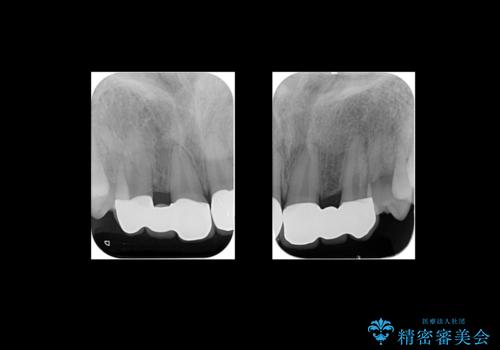

バラバラに位置している前歯の位置を矯正治療で修正してからブリッジを装着しています。

また、全体矯正もご希望でしたので下の歯のがたつきや、すれ違っているかみ合わせも治療しています。

- 前歯ブリッジ85.8万円 (ジルコニアクラウン 12.1万円×6本 仮歯 1.1万円×6本)矯正費用別途費用は治療当時の料金となります

矯正治療によって事前に歯の位置を修正しているため、ダミーの歯の大きさも調整し、自然な仕上がりにしました。また、犬歯のねじれを治してから削っているため、神経をとらずに歯の形を整えることができました。